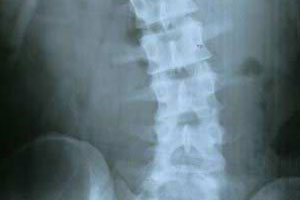

腰椎间盘突出:

腰椎间盘突出主要是由外因、内因、椎间盘本身退行性变等原因而导致的,腰椎间盘突出给患者带来了很大的困扰。那么,腰椎间盘突出症的治疗方法有哪些呢?下面我们一起来了解。